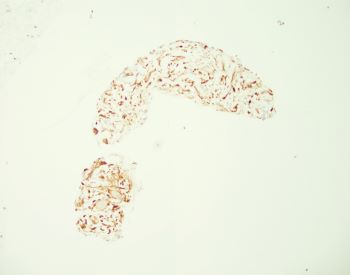

A fine needle aspiration of pancreatic head lesion/mass was performed and the specimen consists of loosely arranged small groups of spindle cells with scant cytoplasm and oval elongated and regular nuclei. Nucleoli are not seen. Ganglion cells are also present (two present in the lower half of the IHC image of the question).

Immunohistochemistry is performed for further characterization. The lesional cells are positive for S100 (shown above) and negative for CD117, DOG1 and desmin. The final diagnosis is neurofibroma.